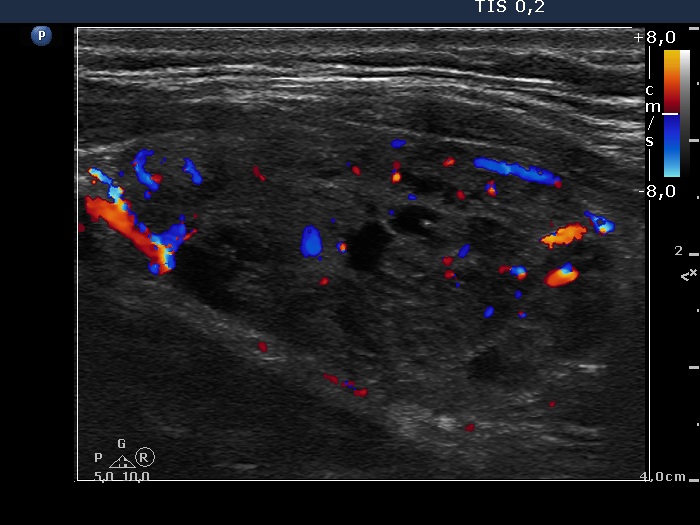

Three years after the first examination (ultrasonographic picture 9)

Left lobe, longitudinal scan, color Doppler mode. The large nodular area presents both perinodular and intranodular blood flow.